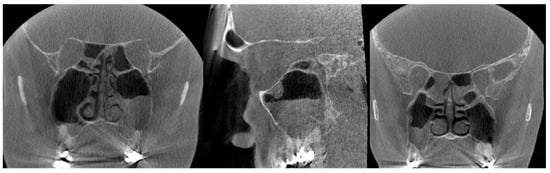

We re-examined all 214 CBCT images to analyze the location and prevalence of all artifacts, even the minor ones, in more detail. All artifacts were recorded in three cross-sectional views, axial, sagittal, and coronal, and in three horizontal levels, as given in Figure 1. As expected, artifacts of any degree were most common at level 1, present in all 214 images. Level 2 artifacts were less frequent, present in 60/214 (28%) of the CBTC images. At level 3, covering the sphenoid, ethmoid, and frontal sinuses, artifacts were recognized in only one image (0.5%) due to a metal plate in the maxilla (Figure 3). Artifacts were equally seen in all coronal, axial, and sagittal views. We also analyzed the interobserver reliability to detect artifacts. In total, 50 CBCT images were selected randomly to calculate the overall agreement of the interobserver reliability. The overall agreement to identify artifacts at level 1 was almost perfect, 0.960, 95% CI 0.90–1.00 (48 out of 50); at level 2, substantial, 0.560, 95% CI 0.42–0.69 (28 out of 50); and at level 3, also almost perfect 0.940, 95% CI 0.87–1.00 (47 out of 50).

The origin of the artifacts in the CBCT images is given in Figure 5. The main origins of the artifacts were large dental fillings or crowns in the upper jaw, being present in 203/214 (95%) of the CBCT images (Figure 6). Endodontic fillings of the maxillary teeth were the reason for artifacts in 111/214 (52%) of the images (Figure 7), followed by fixed dental prostheses and dental implants (Figure 8) causing the artifacts in 28/214 (13%) and 5/214 (2.3%) of the CBCT images, respectively. Other implants in the maxillofacial area were found only in three CBCT images, resulting in artifacts in levels 2 and 3 (Figure 3).

In re-evaluating the 214 CBCT images, we found that artifacts are common in elderly patients, as most of them have had restorative dentition treatments with a wide range of materials used. As an example, the CBCT image given in Figure 6 illustrates the detrimental effect of dental restorations. The magnitude of artifacts in CBCT images caused by materials used in dentistry depends on the atomic weight of the material as well as the size and thickness of the object [22]. According to the literature, titanium implants are the source of detrimental artifacts especially in the CBCT images [15,23,24], as are also the Zirconia implants [25,26,27]. Fiber-reinforced composites (FRC), which are clinically used in cranioplasty surgery, seem to be without detrimental effects in the CBCT images [28]. We have shown earlier that composite materials which consist of at least 20% radio-opacifying BaAlSiO2 fillers can cause artifacts in the CBCT images [29]. In the present study, there were only a few patients with dental (5/214) and maxillofacial implants (3/214), but as shown here, multiple dental implants cause deleterious artifacts (Figure 8).

Figure 3. The coronal slice of the CBCT image shows artifacts induced by a metal plate on the right side of the maxilla.

Figure 6. (Left): The coronal and sagittal CBCT slices present the signs of sinusitis and artifacts induced by dental restorations in the maxilla. Possible apical periodontitis cannot be distinguished accurately because of the artifacts. (Right): The coronal slice of CBCT image presenting mucosal thickening in the paranasal sinuses and artifacts induced by dental restorations hampering the evaluation of the periapical region of the teeth in detail.